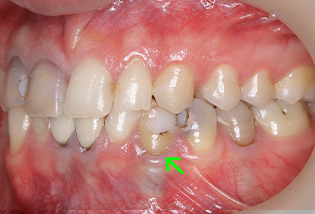

ジルコニアクラウン

の症例

| 年齢・性別 | 20代・男性 |

| 主訴 | 虫歯がある |

| 適応するプラン | 神経の中から治療し、被せ物を装着する |

| 虫歯の範囲 | 神経まで達する虫歯 |

| 治療期間 | 約1ヶ月 |

| 治療回数 | 3〜8回 |

| 治療内容 | 左下の犬歯のプラスチックのつめ物の下が虫歯で、 噛むと痛いという症状があった。 歯の神経まで達する虫歯のため、 歯の神経を4回かけて症状がなくなるまで治療。 防腐剤を詰めて歯の神経の治療は終了した。 その後、歯の土台をたてて白いかぶせ物 (ジルコニアクラウン)を装着した。 |

| 治療費用 | 歯の神経の治療 約2,000円(保険内) かぶせ物 55,000円(税込)(自費) |

| 副作用等 | かみ合わせがとても強い方の場合、 稀に割れてしまうことがあります。 |